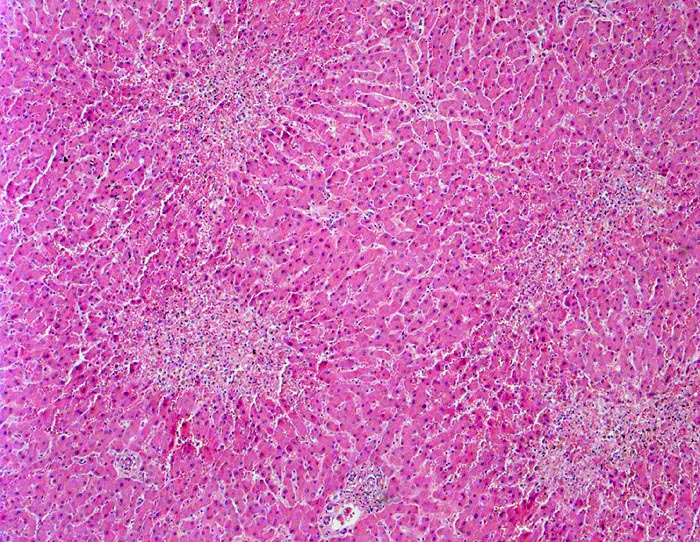

Zonale perizentrale Parenchymnekrosen bei Schock

vaskulär / Durchblutungsstörung

Leber

In der Übersicht erkennt man, dass das Parenchym rund um die Portalfelder in den Zonen 1 und 2 vital und weitgehend unauffällig ist. Um die Zentralvenen sternförmige frische zonale Nekrosen. An einer Stelle schmale zentrozentrale Nekrosebrücke.

Schweres akutes Rechtsherzversagen bei multiplen zentralen und perizentralen Lungenembolien.